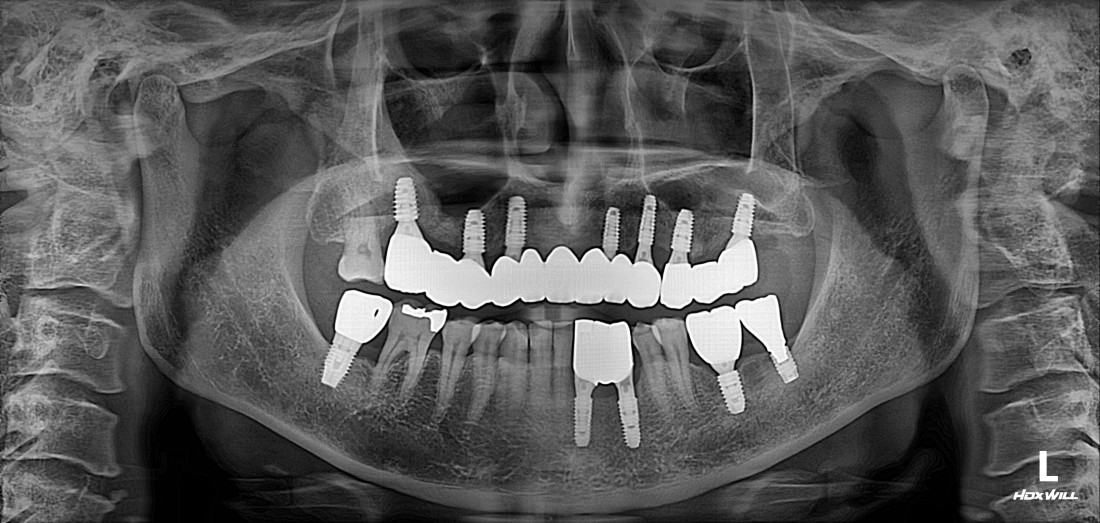

전남광주 임플란트 치과에서는

디지털가이드 임플란트 수술방법으로

한 번에 8개 이상의 임플란트를

심을 수 있습니다.

위, 아래 전체 임플란트를

단 두 번의 수술만으로 완성할 수 있어

임플란트 치과에 자주 내원하지 않으셔도 되고,

붓기 / 출혈 / 통증도 적기 때문에

빠른 회복을 기대할 수 있습니다.